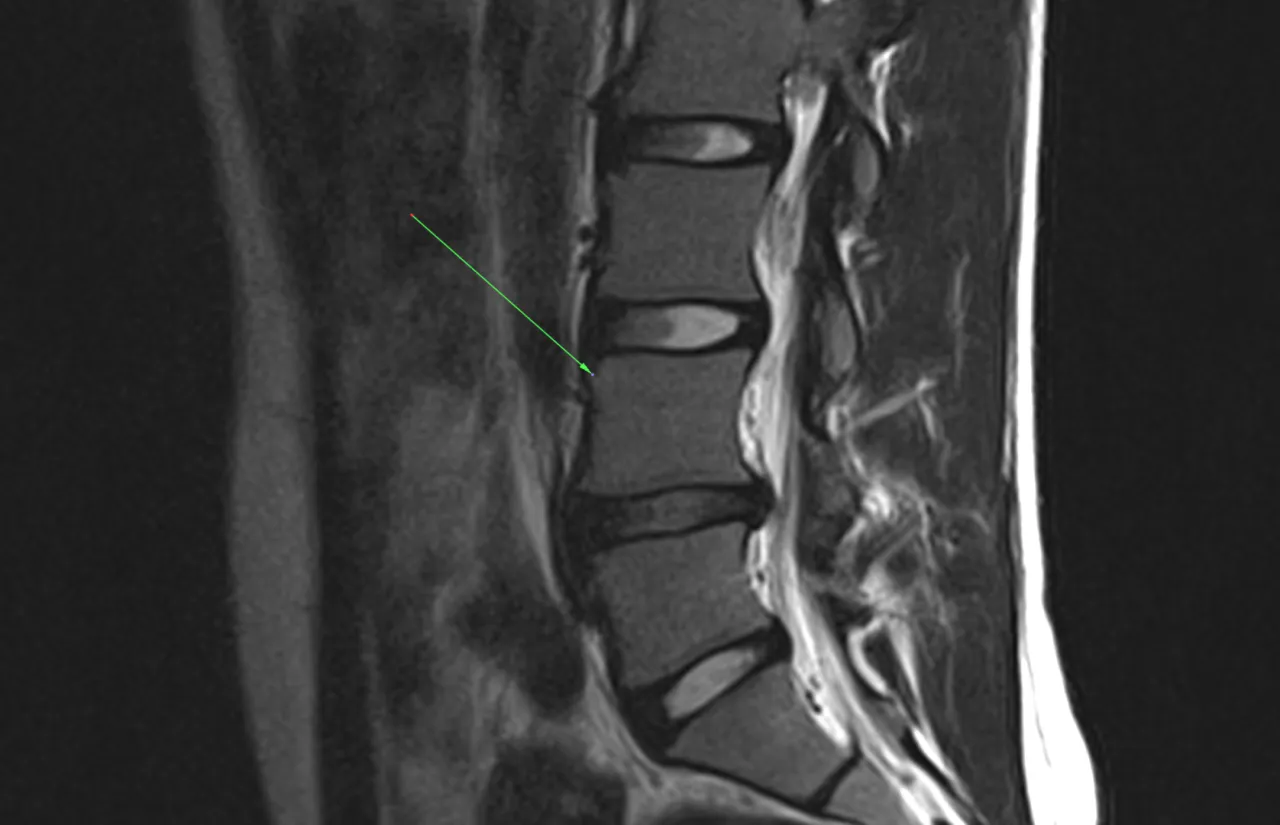

Badania diagnostyczne są kluczowym elementem oceny stanu zdrowia pacjenta z guzkami Schmorla. Pozwalają one na szczegółowe zobrazowanie kręgosłupa oraz określenie stopnia zaawansowania zmian. Wśród najczęściej stosowanych badań znajdują się rezonans magnetyczny (MRI) oraz rentgen. Rezonans magnetyczny dostarcza dokładnych informacji o tkankach miękkich i strukturach nerwowych, podczas gdy rentgen pozwala na ocenę kości i ich ewentualnych deformacji. Te badania są niezbędne do postawienia właściwej diagnozy i zaplanowania dalszego leczenia.| Rodzaj badania | Cel | Typowe wyniki |

| Rezonans magnetyczny (MRI) | Zobrazowanie tkanek miękkich i struktur nerwowych | Obraz guzów, stan nerwów, obecność stanów zapalnych |

| Rentgen | Ocena struktury kości | Deformacje, zmiany zwyrodnieniowe, obecność guzów |